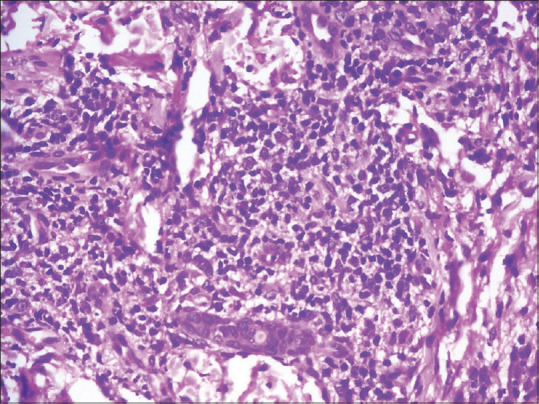

Malignant secondary syphilis presenting with rupioid lesions and moth-eaten alopecia.

恶性继发性梅毒,表现为溃疡和蛀蚀性脱发。